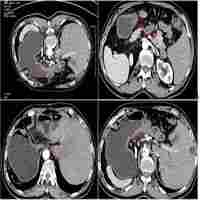

Lung cancer in situs inversus totalis (SIT) - a case report Rak płuca w zespole odwrócenia trzewi - opis przypadku

| Abstract | A case of a 69-year-old patient with bronchogenic large cell cancer of the left lung and metastatic tumor in the right suprarenal gland associated with situs inversus totalis (SIT) is presented. The patient underwent left thoracotomy and laparoscopy with the option of adjuvant chemotherapy afterwards. The SIT diagnosis was based on bronchofiberoscopy, contrast enhanced chest computed tomography and echocardiography as well. At the time of both operations the mirror image anatomy was confirmed. This is the second SIT case treated |